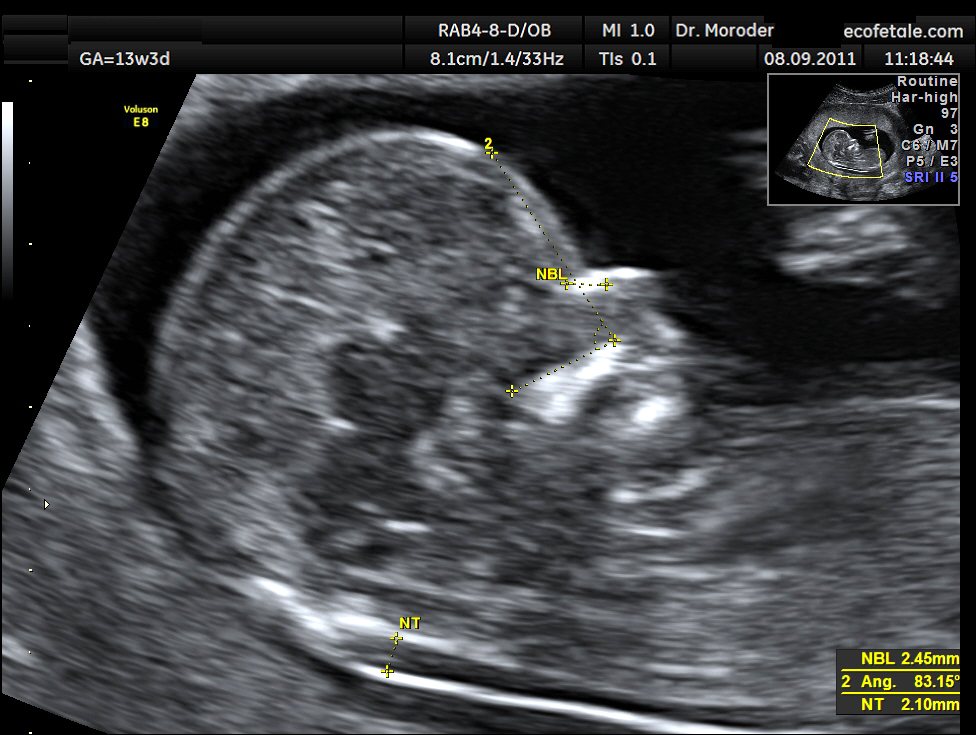

Độ mờ da gáy (tiếng anh là Nuchal translucency) là hình dạng siêu âm của một tập hợp chất lỏng dưới da phía sau cổ thai nhi trong ba tháng đầu của thai kỳ và xuất hiện dưới dạng hình ảnh màu đen hoặc mờ trên màn hình siêu âm. Ở những thai nhi có bất thường nhiễm sắc thể, khiếm khuyết tim và nhiều hội chứng di truyền, độ mờ da gáy sẽ cao hơn.

Độ mờ da gáy (kí hiệu NT) trong hình ảnh siêu âmSiêu âm độ mờ da gáy khi nào?

Trên màn hình siêu âm, phần màu trắng thể hiện làn da của bé và phần màu đen là phần dịch tích tụ sau gáy.